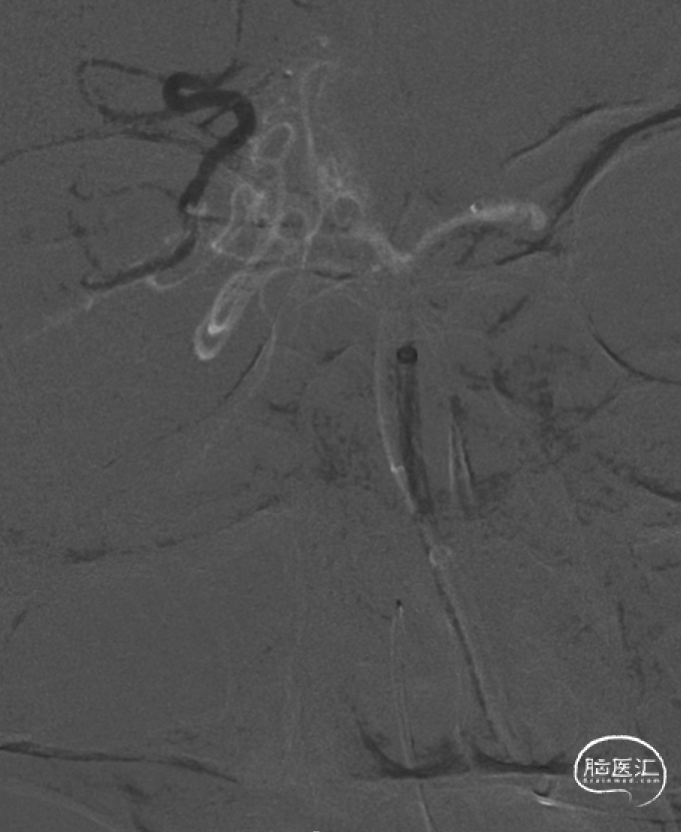

微导丝携带微导管至右侧大脑后动脉P3段,抽拉结合取栓一次见右侧大脑后动脉再通。

微导丝携带微导管至左侧大脑后动脉P3段,抽拉结合取栓一次见左侧大脑后动脉再通。

左侧大脑后动脉P1段发白,观察20min较前好转,血流状态维持良好,结束手术。